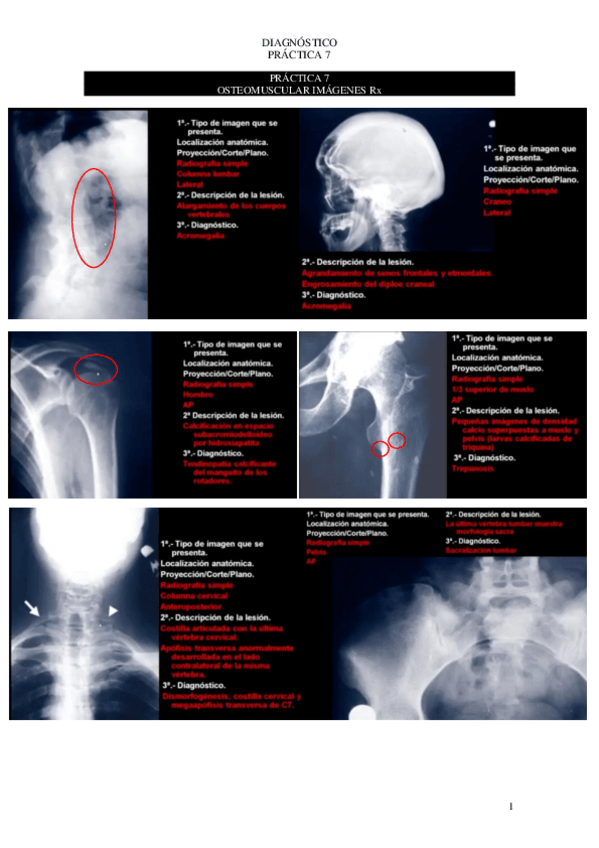

7o-PRACTICAS.pdf